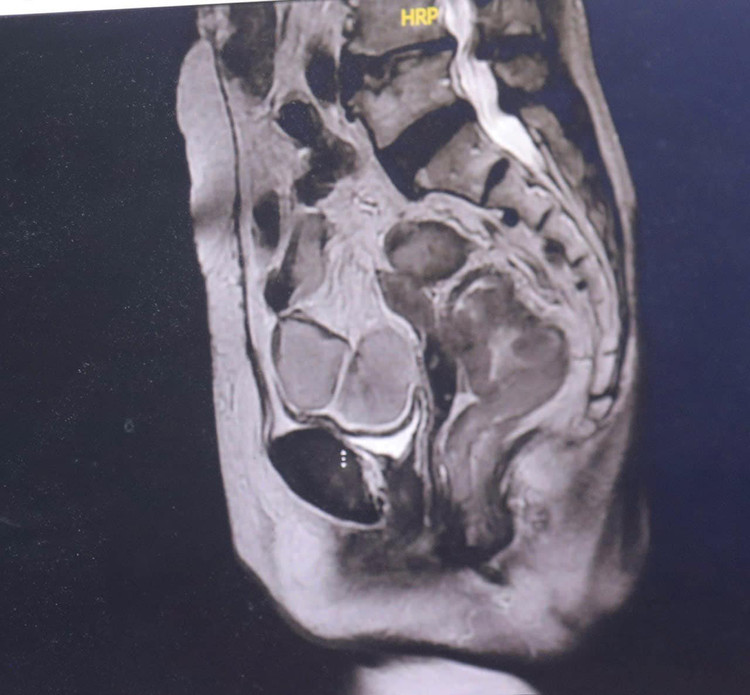

Các bác sĩ đã chỉ định chụp chiếu và làm các xét nghiệm, kết quả cho thấy bệnh nhân T. có tổn thương u trực tràng trung bình cách rìa hậu môn 7cm có kích thước 5x6cm.

U đã phá vỡ thanh mạc trên đại thể, chưa xâm lấn các cơ quan lân cận, tổ chức trực tràng và mô liên kết xung quanh mùn nát. Bệnh nhân được chẩn đoán ung thư trực tràng trung bình T4aN1M0.

| Hình ảnh khối u trên phim chụp - Ảnh BVCC |